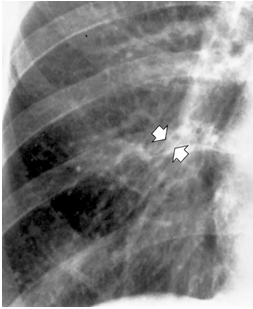

例如,下图是一位慢性支气管炎患者的胸片,箭头指向右肺门附近双轨征

慢性支气管炎患者的胸片:右肺门附近双轨征(箭头) [3,4]仔细观察胸片

气管影,支气管壁增厚形成两条平行的线状阴影,称为双轨征或者轨道征3